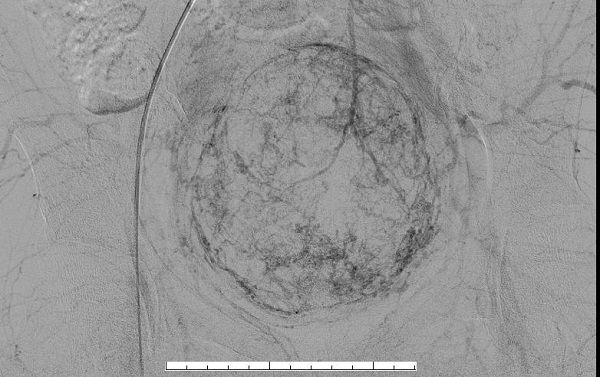

(术前磁共振)

入院后给予抽血检查,随即检验科回报危急值:血红蛋白(46g/L)。立即给予输血治疗后,患者头晕、乏力等症状较前明显好转。完善盆腔磁共振,肌壁巨大子宫肌瘤(10.8cm×8.8cm×8.4cm)。经过制定详细手术计划后,排除手术禁忌,给予行“选择性子宫动脉栓塞术”。